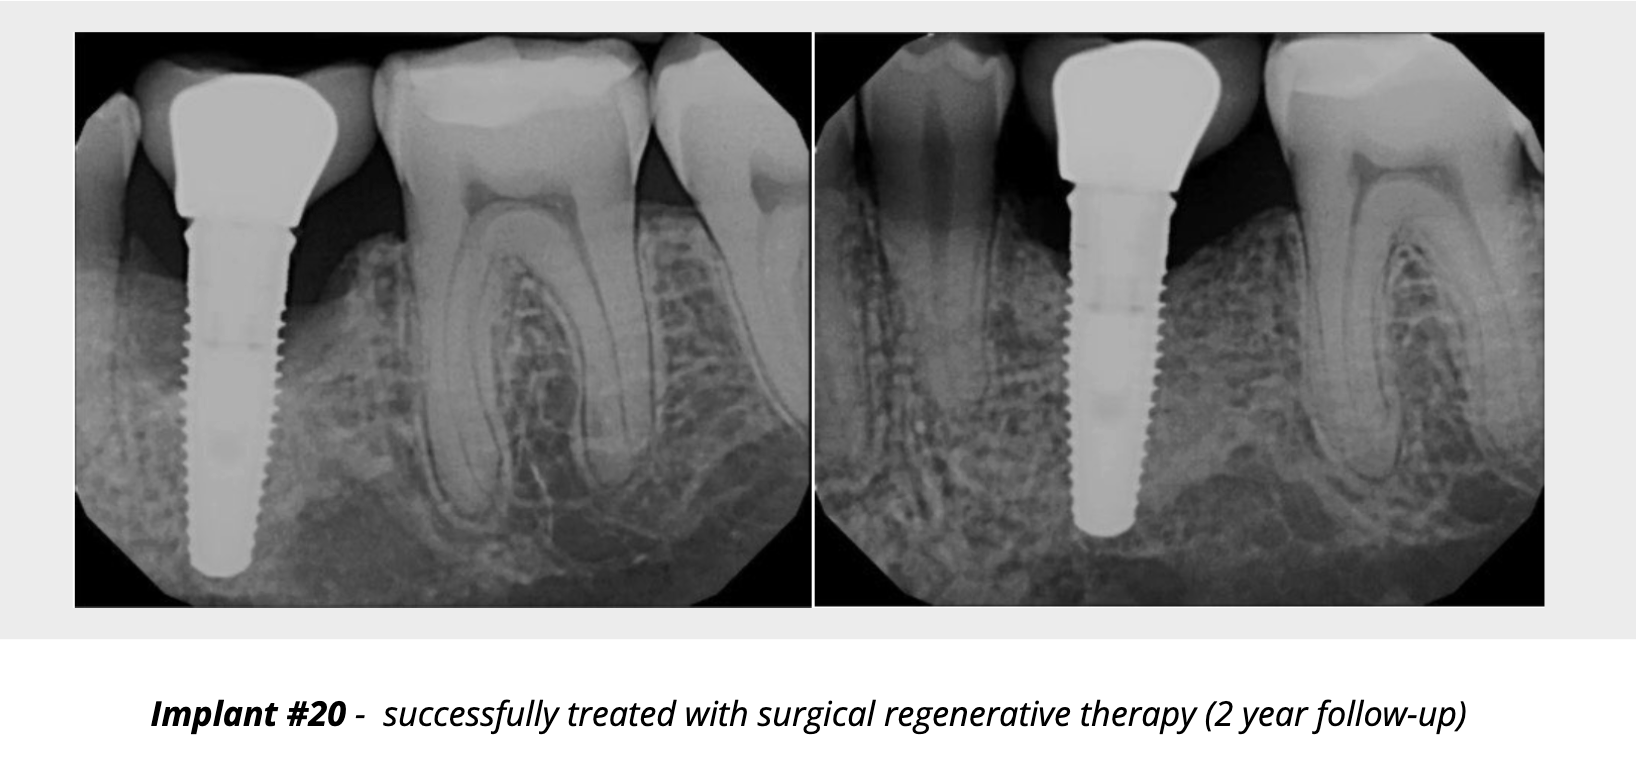

When inflammation progresses to bone loss, we enter the realm of peri-implantitis. The therapeutic goal expands: arrest bone loss, reduce probing depths, resolve inflammation, and ideally regenerate lost supporting structures. While non-surgical therapy is often the first line treatment for peri-implantitis, it has limited efficacy for moderate-to-severe cases. Surgical therapy is often required once non-surgical measures are insufficient. Flap access, debridement, implant surface decontamination, possibly resective or reconstructive surgery, often with grafting materials or membranes, are indicated. There is evidence that surgical therapy can reduce probing depths by 30-50%.